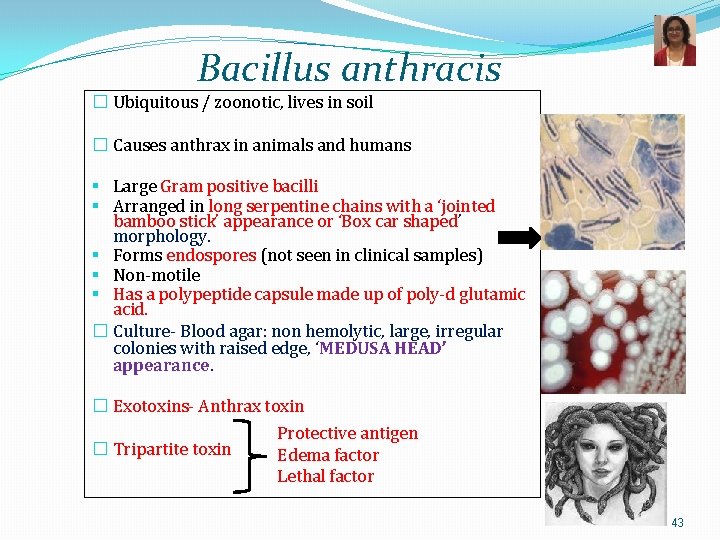

Bacillus anthracis � Ubiquitous / zoonotic, lives in soil � Causes anthrax in animals and humans § Large Gram positive bacilli § Arranged in long serpentine chains with a ‘jointed bamboo stick’ appearance or ‘Box car shaped’ morphology. § Forms endospores (not seen in clinical samples) § Non-motile § Has a polypeptide capsule made up of poly-d glutamic acid. � Culture- Blood agar: non hemolytic, large, irregular colonies with raised edge, ‘MEDUSA HEAD’ appearance. � Exotoxins- Anthrax toxin � Tripartite toxin Protective antigen Edema factor Lethal factor 43